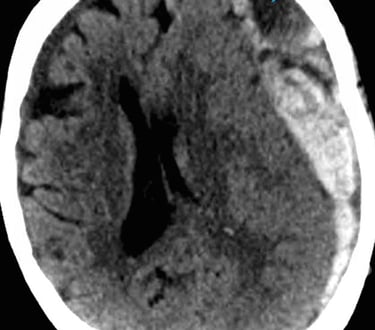

Neurocirugía

Hidrocefalia

Tumores cerebrales y espinales

Aneurismas cerebrales

Traumatismos craneoencefálicos

Hemorragias cerebrales